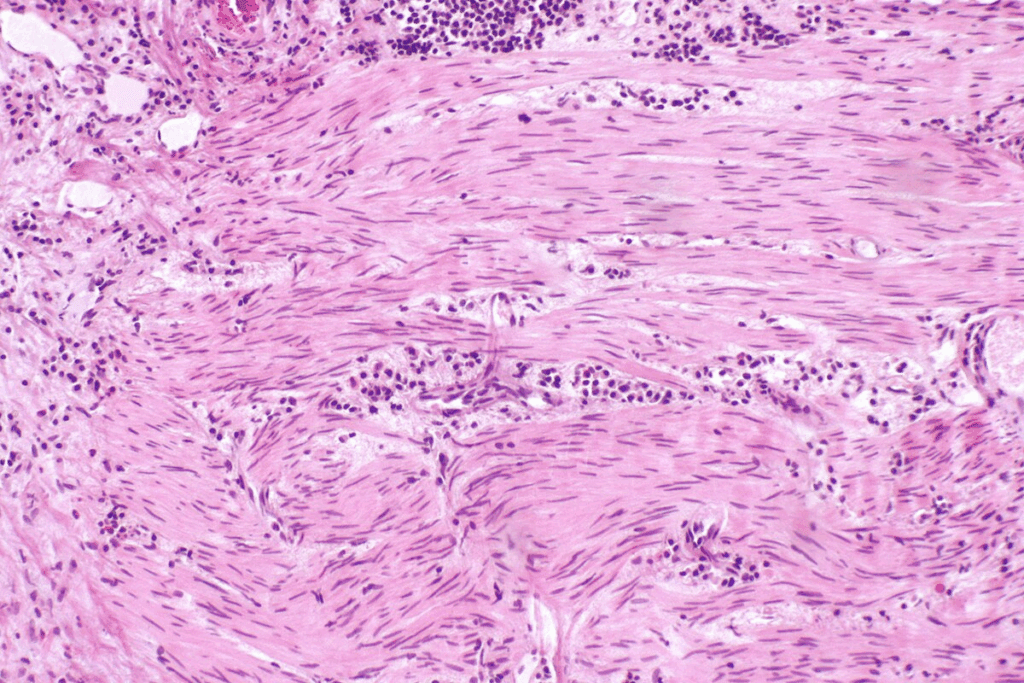

Bladder cancer is divided into several types based on where the cancer starts. The most common type is urothelial carcinoma, also known as transitional cell carcinoma. It starts in the urothelial cells lining the bladder. Other types, like squamous cell carcinoma and adenocarcinoma, affect different cells.

Grading of Bladder Cancer Tumors

Bladder cancer tumors are also graded based on how much they look like normal cells. The grade shows how fast the cancer is likely to grow and spread. Tumors are usually classified as low grade or high grade. Low-grade tumors grow and spread slowly, while high-grade tumors are more aggressive.